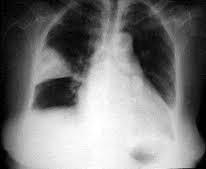

Ателектаз легкого — симптомы и диагностика . Симптомы ателектаза легкого очень часто зависят от степени поражения и быстроты развития заболевания .

Компрессионный ателектаз, или коллапс, легкого . Это состояние вызывается сдавлением легочных тканей снаружи, а также скоплением в плевральной полости экссудата, воздуха, крови или гноя .

Ателектаз легкого — это спадение какого-либо участка легочной ткани, возникающее вследствие сдавливания легкого извне либо закупорки просвета бронха . . . . фото, симптомы у взрослых, лечение . . .

Ателектаз — это спадение всего легкого (коллапс) или его части вследствие нарушения вентиляции, обусловленной обтурацией бронха или сдавлением легкого .

Ателектаз легкого — это патологическое состояние, при котором целое легкое или его часть спадается (происходит сближение и сжатие стенок легкого, при этом воздух из данного участка выходит) и выключается из . . .

Ателектаз легкого: на рентгеновском снимке или что это такое у взрослого, лечение дисковидной патологии или причины ее появления . Ателектаз - патологическое состояние, при котором ткань . . .